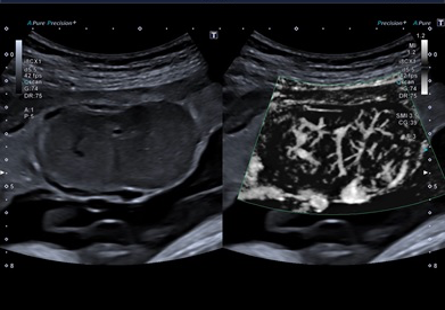

Технологія Superb Microvascular Imaging (SMI)

Технологія Superb Microvascular Imaging (SMI), яка доступна ексклюзивно для ультразвукових систем Canon, дає значний якісний прогрес у візуалізації судин, особливо дрібних і з найповільнішим кровотоком. Такого ефекту вдалося досягти завдяки інноваційному алгоритму фільтрації шумів на доплерівському зображенні. Звичайні наявні методи візуалізації кровотоку обов'язково використовують жорсткі шумові фільтри, додатково усуваючи найнижчі швидкості. Без цих фільтрів, зображення було б здебільшого шумним. Фільтрація, яка застосовується в режимі SMI, вибірково відфільтровує сигнали хаотичних рухів, залишаючи лише впорядковані рухи крові.

Технологія SMI має два режими:

• cSMI - відображається, як і інші доплери, у вигляді кольорового зображення судин на фоні тканини в межах обраної області інтересу (ROI),

• mSMI — у цьому режимі сигнал тканини пригнічується в межах доплерівської досліджуваної області, залишаючи лише зображення кровотоку; цей режим є більш чутливим, та найчастіше використовується в режимі подвійного вікна з повним зображенням у B-режимі на іншій половині екрана.

Бувають випадки, коли SMI є єдиним інструментом, який дозволяє виявити ізоехогенні інтерстиціальні вузли, наприклад у щитоподібній залозі, підшлунковій залозі, нирках тощо. Можливість точного картування васкуляризації паренхіми також дозволяє, наприклад, оцінити стан трансплантованої нирки.

Підвищена васкуляризація трапляється не тільки при пухлинних ураженнях, але і в запальних і травматичних вогнищах. У цьому контексті SMI є цінним інструментом для ортопедів для оцінки змін опорно-рухового апарату. При чому, як для початкової оцінки змін в результаті гострих або хронічних травм, так і для їх подальшого моніторингу.